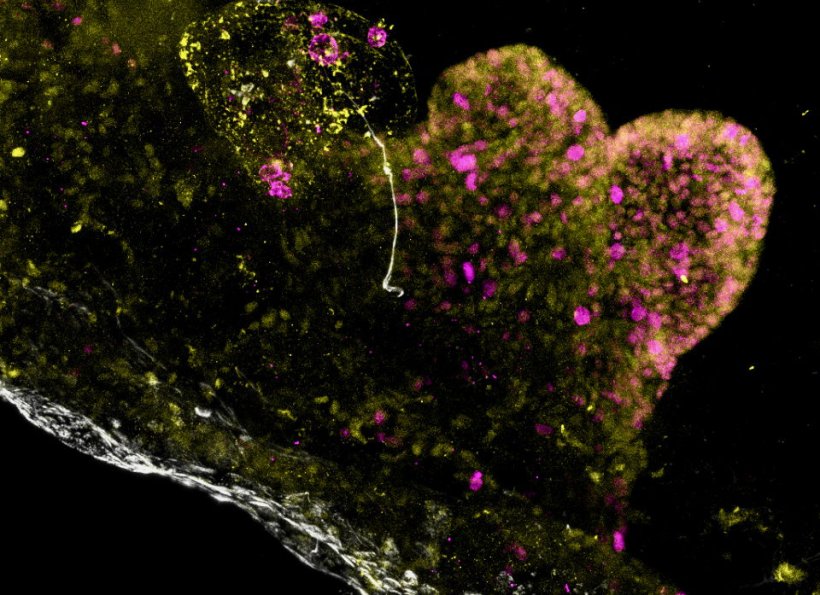

Image source: Jones BC, Benedetti G, Calà G et al., Nature Biomedical Engineering 2026 (CC BY 4.0)

They grew separate organoids for each of the three main stomach regions and then combined – or “assembled” – them into a single version, known as an assembloid version. This is the first time this has been successfully achieved.

The research team found that not only did each component part retain the characteristics of the area of the stomach from which it was grown, but those component parts communicated with each other in the same way that the full-sized human organ does. The assembloids were also able to produce stomach acid, which is a key function of the stomach and helps the body digest food. Researchers then used this technique to model a very rare genetic stomach disease, which they say could open up the possibility of using the system to study more common gastric disorders that have so far been poorly understood.